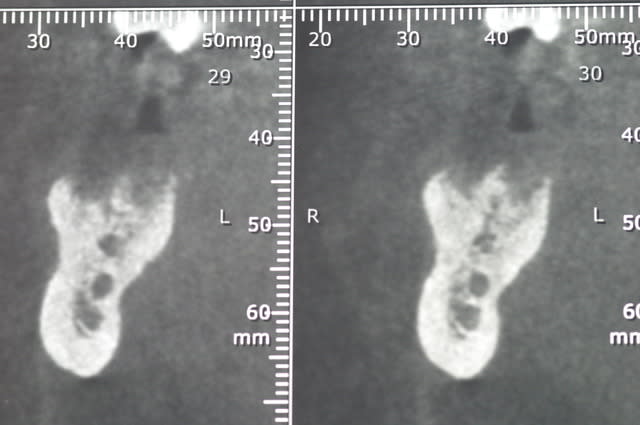

ci joint les photos des coupes scanner d'un patient à qui j'ai proposé de poser un implant afin de remplacer la 36. sur les coupes, on vois nettement le dédoublement du NAI.